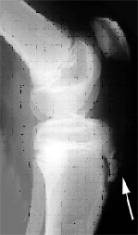

Es una entidad clínica en la que se encuentra alterado en normal funcionamiento de esta articulación ocasionado por la descompensación de las estructuras retentoras de la misma (óseas y/o de partes blandas).

La sintomatología clínica es muy variada pudiendo manifestarse en forma de dolor rotuliano , subluxación y luxación de rótula , esporádica o inveterada , y fracturas osteocondrales asociadas a episodios de luxación. Deben valorarse detenidamente los estabilizadores óseos y músculo-ligamentosos que participan en el funcionamiento de esta articulación a la hora de plantearse el tratamiento de esta patología.

Existen diferentes intervenciones descritas en función de si es preciso realizar una realineación del aparato extensor a nivel proximal , distal o ambos y en función de la presencia del cartílago de crecimiento fértil.

En los pacientes en edad pediátrica es muy frecuente la asociación de esta entidad a la presencia de un rótula alta (determinada por el índice de Insall) por lo que utilizamos la técnica descrita por Galleazzi mediante tenodesis con tendón semitendinoso autólogo y sección artroscópica del alerón rotuliano externo.